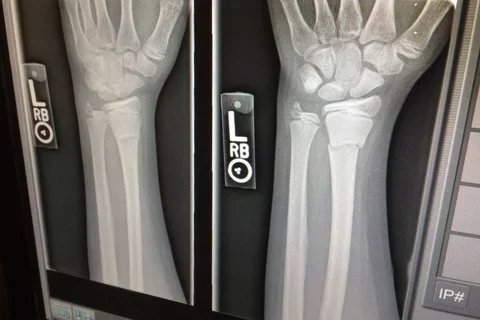

Even fractures in arm, wrist increase risk for future breaks in postmenopausal women

Current guidelines for managing osteoporosis specifically call out hip or spine fractures for increasing the risk for subsequent bone breaks. But a new UCLA-led study suggests that fractures in the arm, wrist, leg and other parts of the body should also set off alarm bells.

The researchers found that among postmenopausal women, initial fractures of the lower arm or wrist, upper arm or shoulder, upper leg, knee, lower leg or ankle, and hip or pelvis were associated with an approximately three- to six-fold increase in risk for subsequent fractures. That finding held for all of the age groups studied, with higher risks being more pronounced among non-Hispanic Black, Hispanic or Latina, and Asian Pacific Islander women than among non-Hispanic White women.